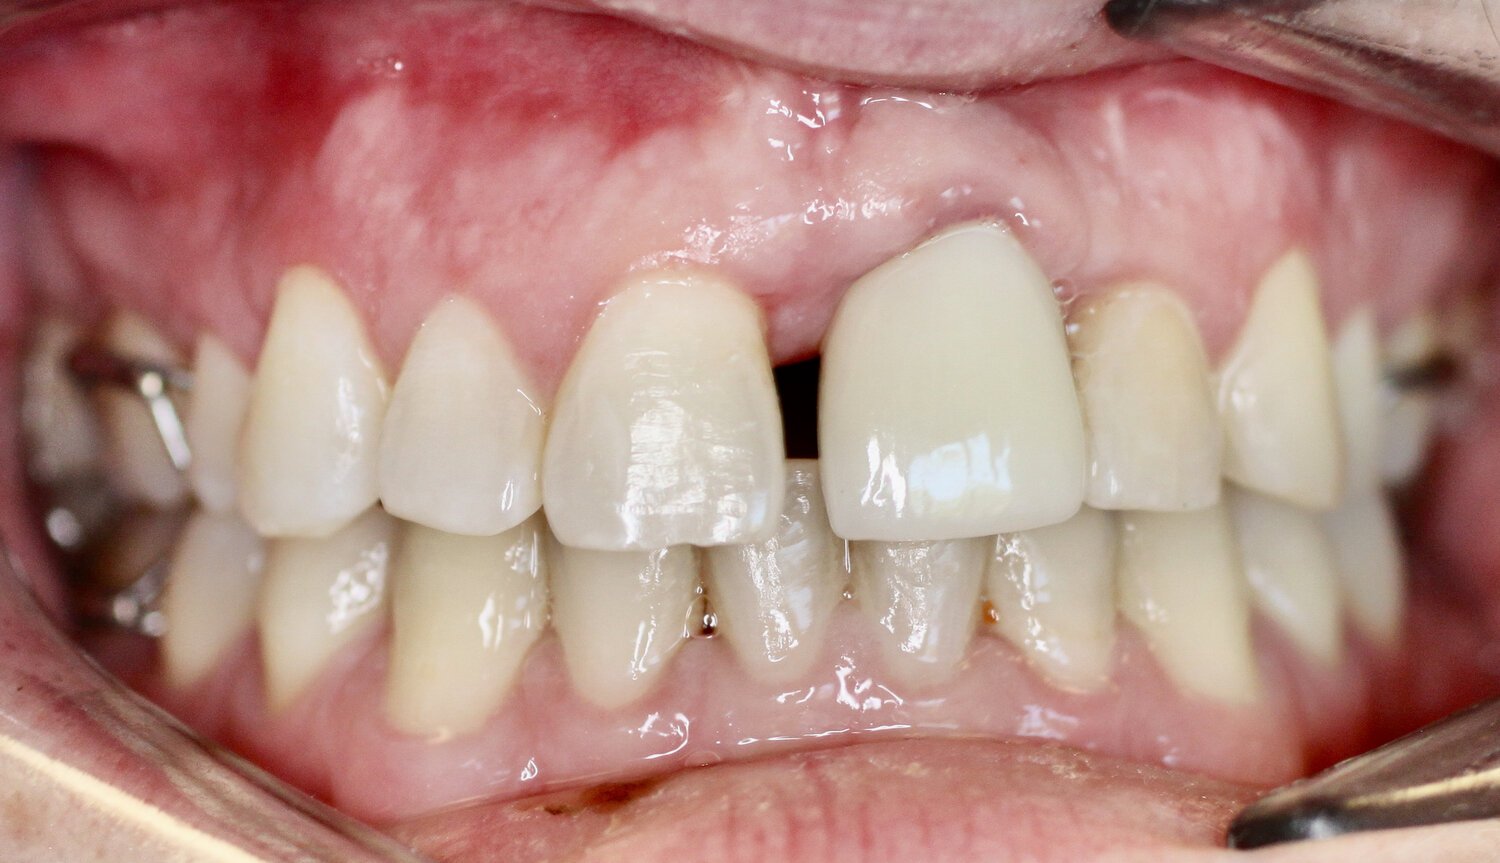

As we age, crowned teeth later can require extraction. Bioclear offers an innovative option to avert this outcome. Bio-clear is the best option for closing black triangles – the dark space between two teeth and the gums – without shaving the teeth down for porcelain veneers. The Bioclear method has modernized the technique for composite solutions.

BEFORE

AFTER